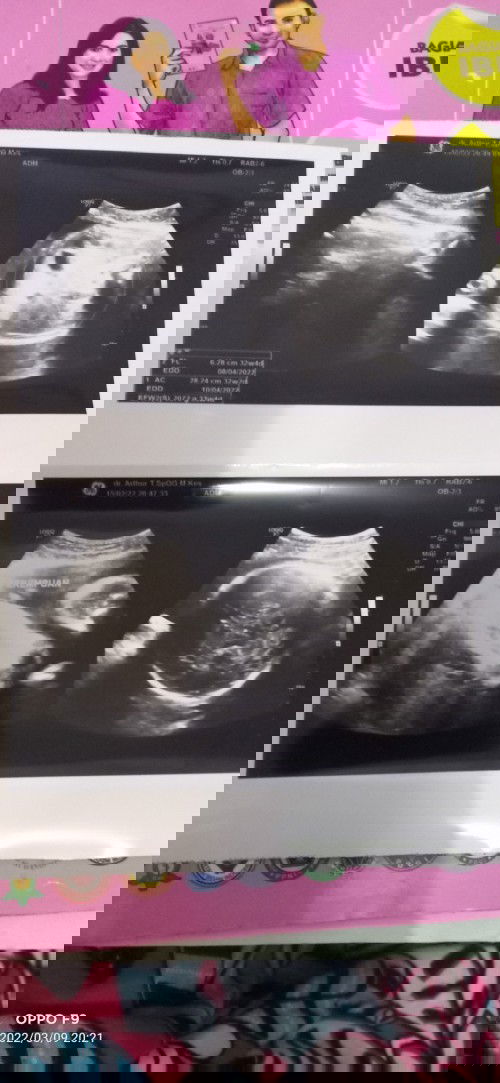

bun mau nanya bun.ni sya sudah hamil 35 minggu..kalo gerakan baby lebih sering sebelah kiri posisi janin gmn y bun.karna perut ku jadi menonjol sebelah kiri..itu bokong nya atau kepala ya bun.pas usg kmren lupa nnya posisi kepala dmn.